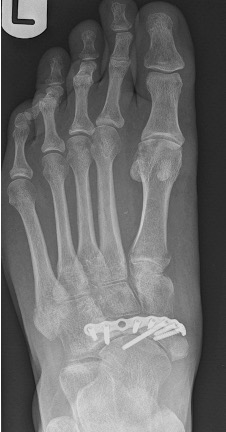

- anatomic anomaly e.g. relatively long 2nd MT compared to the 1st MT (Figure 1)

Figure 1: DP radiographic view of a long 2nd metatarsal